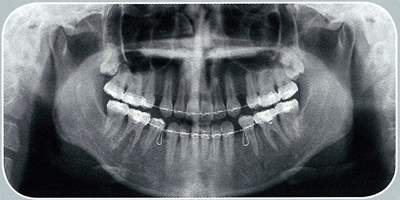

歯科用3DCT

3DCT

歯科用3DCT導入し、大規模病院と同じ診断と診療が可能です。

歯科用3DCTは、コンピューターを駆使したデータ処理と画像との再構成による3次元的な画像を作成することができ、360度全ての角度から見る事が出来ます。今までのX線では映らなかった部分も、はっきり映る様になりました。

歯科用3DCTで出来ること

従来、大規模病院でしか設備していなかった歯科用CTですが、よしもと歯科・矯正が導入してより正確な診断が出来る様になりました。以下の診療にとても効果的で、信頼性を高める事が出来ます。